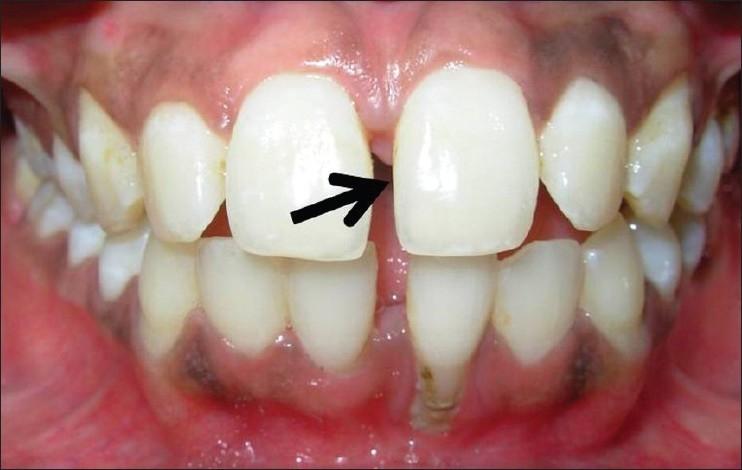

Turner's syndrome is a disorder in females characterized by the absence of all or part of a normal second sex chromosome. It is typically characterized by the combination of physical features and cytogenetics in females. Physical features include short stature, primary amenorrhea, hypogonadism, low hair line at the back of the neck, and digital anomalies. Most affected patients have a 45XO monosomy, but the presence of an abnormal chromosome or mosaicism of 45X with another cell line can also fulfill the criteria. Features seen in the oral cavity of patients diagnosed with Turner's syndrome include high palatal vault, hypoplastic mandible, prematurely erupting teeth, and orthodontic anomalies. A case of Turner's syndrome with localized aggressive periodontitis has been reported here.

特纳综合征是一种女性疾病,其特征是正常的第二条性染色体全部或部分缺失。它通常由女性的身体特征和细胞遗传学特征共同表现出来。身体特征包括身材矮小、原发性闭经、性腺功能减退、颈后发际线低和手指异常。大多数受影响的患者有45,XO单体型,但存在异常染色体或45,X与另一种细胞系的嵌合体也可符合诊断标准。被诊断为特纳综合征的患者口腔中可见的特征包括高腭穹窿、下颌发育不全、牙齿过早萌出和正畸异常。本文报道了一例伴有局限性侵袭性牙周炎的特纳综合征病例。